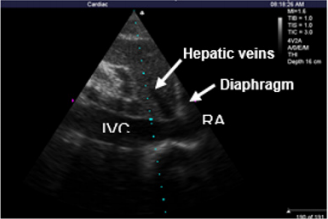

Ultrasonic Testing and PPV Monitoring Method: In complete mechanical ventilation control mode, below indexes were measured by M-Turbo bedside portable ultrasonic apparatus of SonoSite (America): ①CO (cardiac output) ②measuring SV and recording SVV %=(SVmax﹣Svmin)/SVmean, SVmax and SVmin being the mean value of 4 values in 30s, SVmean being the mean value of all values. ③Measurements of IVCdmax , IVCdmin and dIVC were performed from long-axis 2-dimensional subxiphoid views using M mode (Figure1), All measurements were made within 2 cm of the RA origin of the IVC(Figure2), dIVC= (IVCdmax − IVCdmin)/0.5(IVCdmax + IVCdmin) [13]. Ultrasonic testing were respectively conducted by an experienced ultrasound diagnostics doctor and a trained ICU doctor. Each observation indicator was took the average after being measured three times. During mechanical ventilation, the arterial pressure waveform was drawn from invasive arterial pressure monitor, recording PPmax and PPmin, PPV(%)=( PPmax-PPmin) /[(PPmax+PPmin)/2]×100%[20].